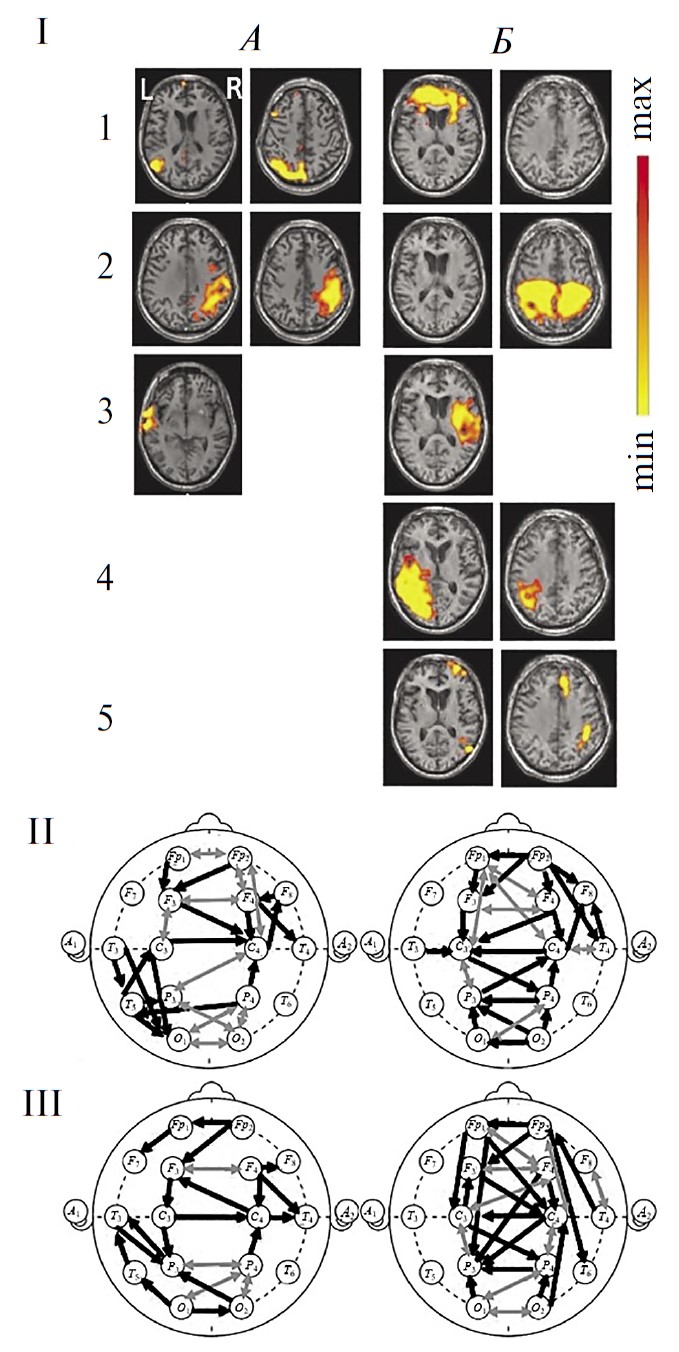

У здоровых испытуемых при групповом анализе RSN фМРТ были верифицировны все 6 сетей, указанных во введении в качестве наиболее значимых для восстановления сознания (рис. 1, А). Большинство из них (за исключением лобно-теменных) имеют симметричную билатеральную топографию, отражая наличие устойчивых межполушарных структурно-функциональных взаимодействий. В трех сетях (DMN, лобно-теменная, речевая) фокусы активности представлены как в лобных, так и в теменных (задне-височных) областях в пределах одного полушария, указывая на сохранность функционирования лобно-теменного пространства, необходимого для сознательной деятельности [1, 51, 52].

Рис. 1. Функциональные сети функциональной магнитно-резонансной томографии (фМРТ) и коннективность ЭЭГ-диапазона 1–15 Гц у здоровых испытуемых в состоянии покоя (n = 15).

А — усредненные по группе испытуемых RSN фМРТ: 1 – DMN, 2 - сенсомоторная, 3 – сеть управляющих функций (исполнительного контроля), 4 – лобно-теменная, 5 – слуховая, 6 – речевая. Шкала справа характеризует уровень максимальной интенсивности сети. Б, В — усредненная в этой же группе испытуемых коннективность ЭЭГ по корреляции Пирсона. Черные линии — однонаправленные связи, серые — двунаправленные, согласно методу причинности Грейнджера. Б — коннективности, рассчитанные на непрерывных записях, В — в режиме псевдо-ВП. Г — зоны концентрации функциональных связей ЭЭГ: а — лобные, б — височно-передневисочные, в — центральные, г — затылочно-теменные.

На рис. 1 представлены также результаты групповой оценки коннективности ЭЭГ диапазона 1–15 Гц этих испытуемых: при непрерывной записи состояния покоя (рис. 1, Б) и в режиме псевдо-ВП (рис. 1, В). На обеих схемах видно значительное число внутри- и особенно межполушарных связей, превышающих уровень корреляции Пирсона 0.5. Многие из них являются разнонаправленными (согласно методу причинности Грейнджера). Важно подчеркнуть, что паттерны связей характеризуются выраженным сходством друг с другом при обоих методах расчета коннективности. Хотя число отобранных связей несущественно меньше при расчете в режиме псевдо-ВП: 33 и 29 соответственно. Особенностью непрерывных записей ЭЭГ является также более частая встречаемость (на 7) двунаправленных связей.

Общее количество коннективностей ЭЭГ преобладает в передних корковых областях. В характере внутриполушарных связей, в первую очередь для непрерывных реализаций ЭЭГ (рис. 1, Б), можно отметить преимущественную правостороннюю направленность (по Грэйджеру) и превалирование их числа в правом полушарии, что, согласно литературным данным может рассматриваться как отражение возможно большей сопряженности этой гемисферы с ощущением своего тела [53] и самоосознанием [54].

Выделить на рис. 1 на схемах Б и В локусы топографического соответствия отдельным сетям фМРТ покоя затруднительно. Однако можно отметить несколько корковых областей, характеризующихся концентрацией функциональных связей: симметричные лобные, центральные, затылочно-теменные, а также височно-передневисочные. Топография этих локусов коннективности ЭЭГ (рис. 1, Г) совпадает с активными зонами сразу нескольких сетей фМРТ покоя: DMN, сенсомоторной, управляющих функций, слуховой и речевой. Можно полагать, что указанные области концентрации связей ЭЭГ можно рассматривать в качестве зон межсетевой коннективности, наличие которой отмечено в ряде публикаций в качестве значимой для восстановления сознания [43, 55].

На рис. 2, I представлены изображения RSN фМРТ этого пациента (из числа перечисленных в методике), выявляемых до (рис. 2, I, А) и после рТМС (рис. 2, I, Б) на идентичных аксиальных срезах мозга. В первом исследовании, на фоне вегетативного состояния, удалось верифицировать компоненты лишь 3-х из 6 исследуемых RSN (рис. 2, I, A): DMN, cенсомоторной и слуховой. Однако эти сети резко отличны от нормы асимметричностью и фрагментарностью. В сети DMN доминирует левополушарный каудальный (затылочный) компонент при значительной редукции лобного. Сенсомотороная сеть представлена компонентами в глубинных отделах правого полушария. Слуховая — левосторонней активностью в базальных отделах.

Рис. 2. Динамика сетей покоя функциональной магнитно-резонансной томографии (фМРТ) и коннективности ЭЭГ-диапазона 1–15 Гц в наблюдении 1.

A — исследование 1 (до ритмической транскраниальной магнитной стимуляции (рТМС)), вегетативное состояние; Б — исследование 2 (через 5 дней после курсовой рTMС), состояние, переходное к мутизму с пониманием речи. I — RSN фМРТ: 1 – DMN, 2 – сенсомоторная, 3 – слуховая, 4 – речевая, 5 – лобно-теменная. Шкала справа как на рис. 1. II — коннективность ЭЭГ покоя в непрерывной записи. III — коннективность ЭЭГ покоя в режиме псевдо-ВП. Обозначения линий см. рис. 1.

Во втором исследовании, при переходе к стадии МПР (рис. 2, I, Б), у пациента были выявлены уже 5 RSN фМРТ за счет составляющих лобно-теменной и речевой сетей. Наряду с этим, обращает на себя внимание повышение интенсивности выраженных ранее RSN, подтвержденное количественно (рис. 3), и изменение их пространственной организации. Так, увеличилась билатеральная интенсивность лобного компонента сети DMN, а также моторной коры обоих полушарий в сенсомоторной сети. Выражена распространенная активность височной сети в правой гемисфере. Появились компоненты двух RSN, отсутствовавшие до стимуляции: речевой слева и правой лобно-теменной.

По данным коннективности ЭЭГ покоя (рис. 2, II и III), при первом исследовании и в непрерывных записях ЭЭГ (рис. 2, A, II), и в режиме псевдо-ВП (рис. 2, A, III) отмечается выраженная редукция межполушарных связей, в особенности диагональных. В первую очередь это касается лобной и моторной зон межсетевой интеграции. Кроме того, обеднены внутриполушарные взаимодействия, особенно в передних отделах обоих полушарий, а также затылочно-теменно-височные связи справа. Вместе с тем, представлены не характерные для нормы коннективности ЭЭГ в затылочно-теменно-центральной области левого полушария. Эти особенности ЭЭГ согласуются с асимметричностью компонентов всех выявленных сетей покоя фМРТ и их фрагментарной представленности в пределах полушария.

Во втором исследовании и в непрерывных записях ЭЭГ (рис. 2, Б, II), и в режиме псевдо-ВП (рис. 2, Б, III) наблюдается увеличение числа межполушарных связей ЭЭГ лобно-центральных и затылочно-теменных областей. Эти изменения согласуются с восстановлением билатеральной структуры сетей управляющих функций и сенсомоторной фМРТ покоя (рис. 2, Б, I, 1-2). Кроме того, выявляются двухсторонние внутриполушарные лобно-центральные коннективности ЭЭГ. В режиме псевдо-ВП более отчетливо выражено увеличение числа протяженных внутриполушарных взаимодействий: лобно-теменной слева, а также лобно-височных и затылочно-центральной справа. Перестройки внутриполушарных связей ЭЭГ согласуются появлением компонентов правой лобно-теменной, а также речевой сетей фМРТ покоя.

Таким образом, в наблюдении 1 прослеживается явная тенденция к нормализации пространственной организации связей ЭЭГ и восстановлению ряда локусов межсетевой коннективности — наряду с позитивными изменениями сетей покоя фМРТ.